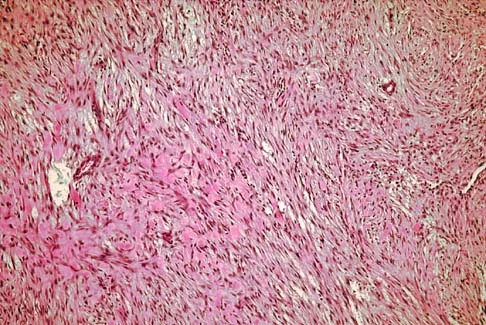

A 19-year-old girl has had pain and swelling in the right ankle for the past 4 months. She denies any history of trauma. Examination reveals a small soft-tissue mass over the anterior aspect of the ankle and slight pain with range of motion of the ankle joint. The examination is otherwise unremarkable. A radiograph and MRI scan are shown in Figures 45a and 45b, and biopsy specimens are shown in Figures 45c and 45d. What is the most likely diagnosis?